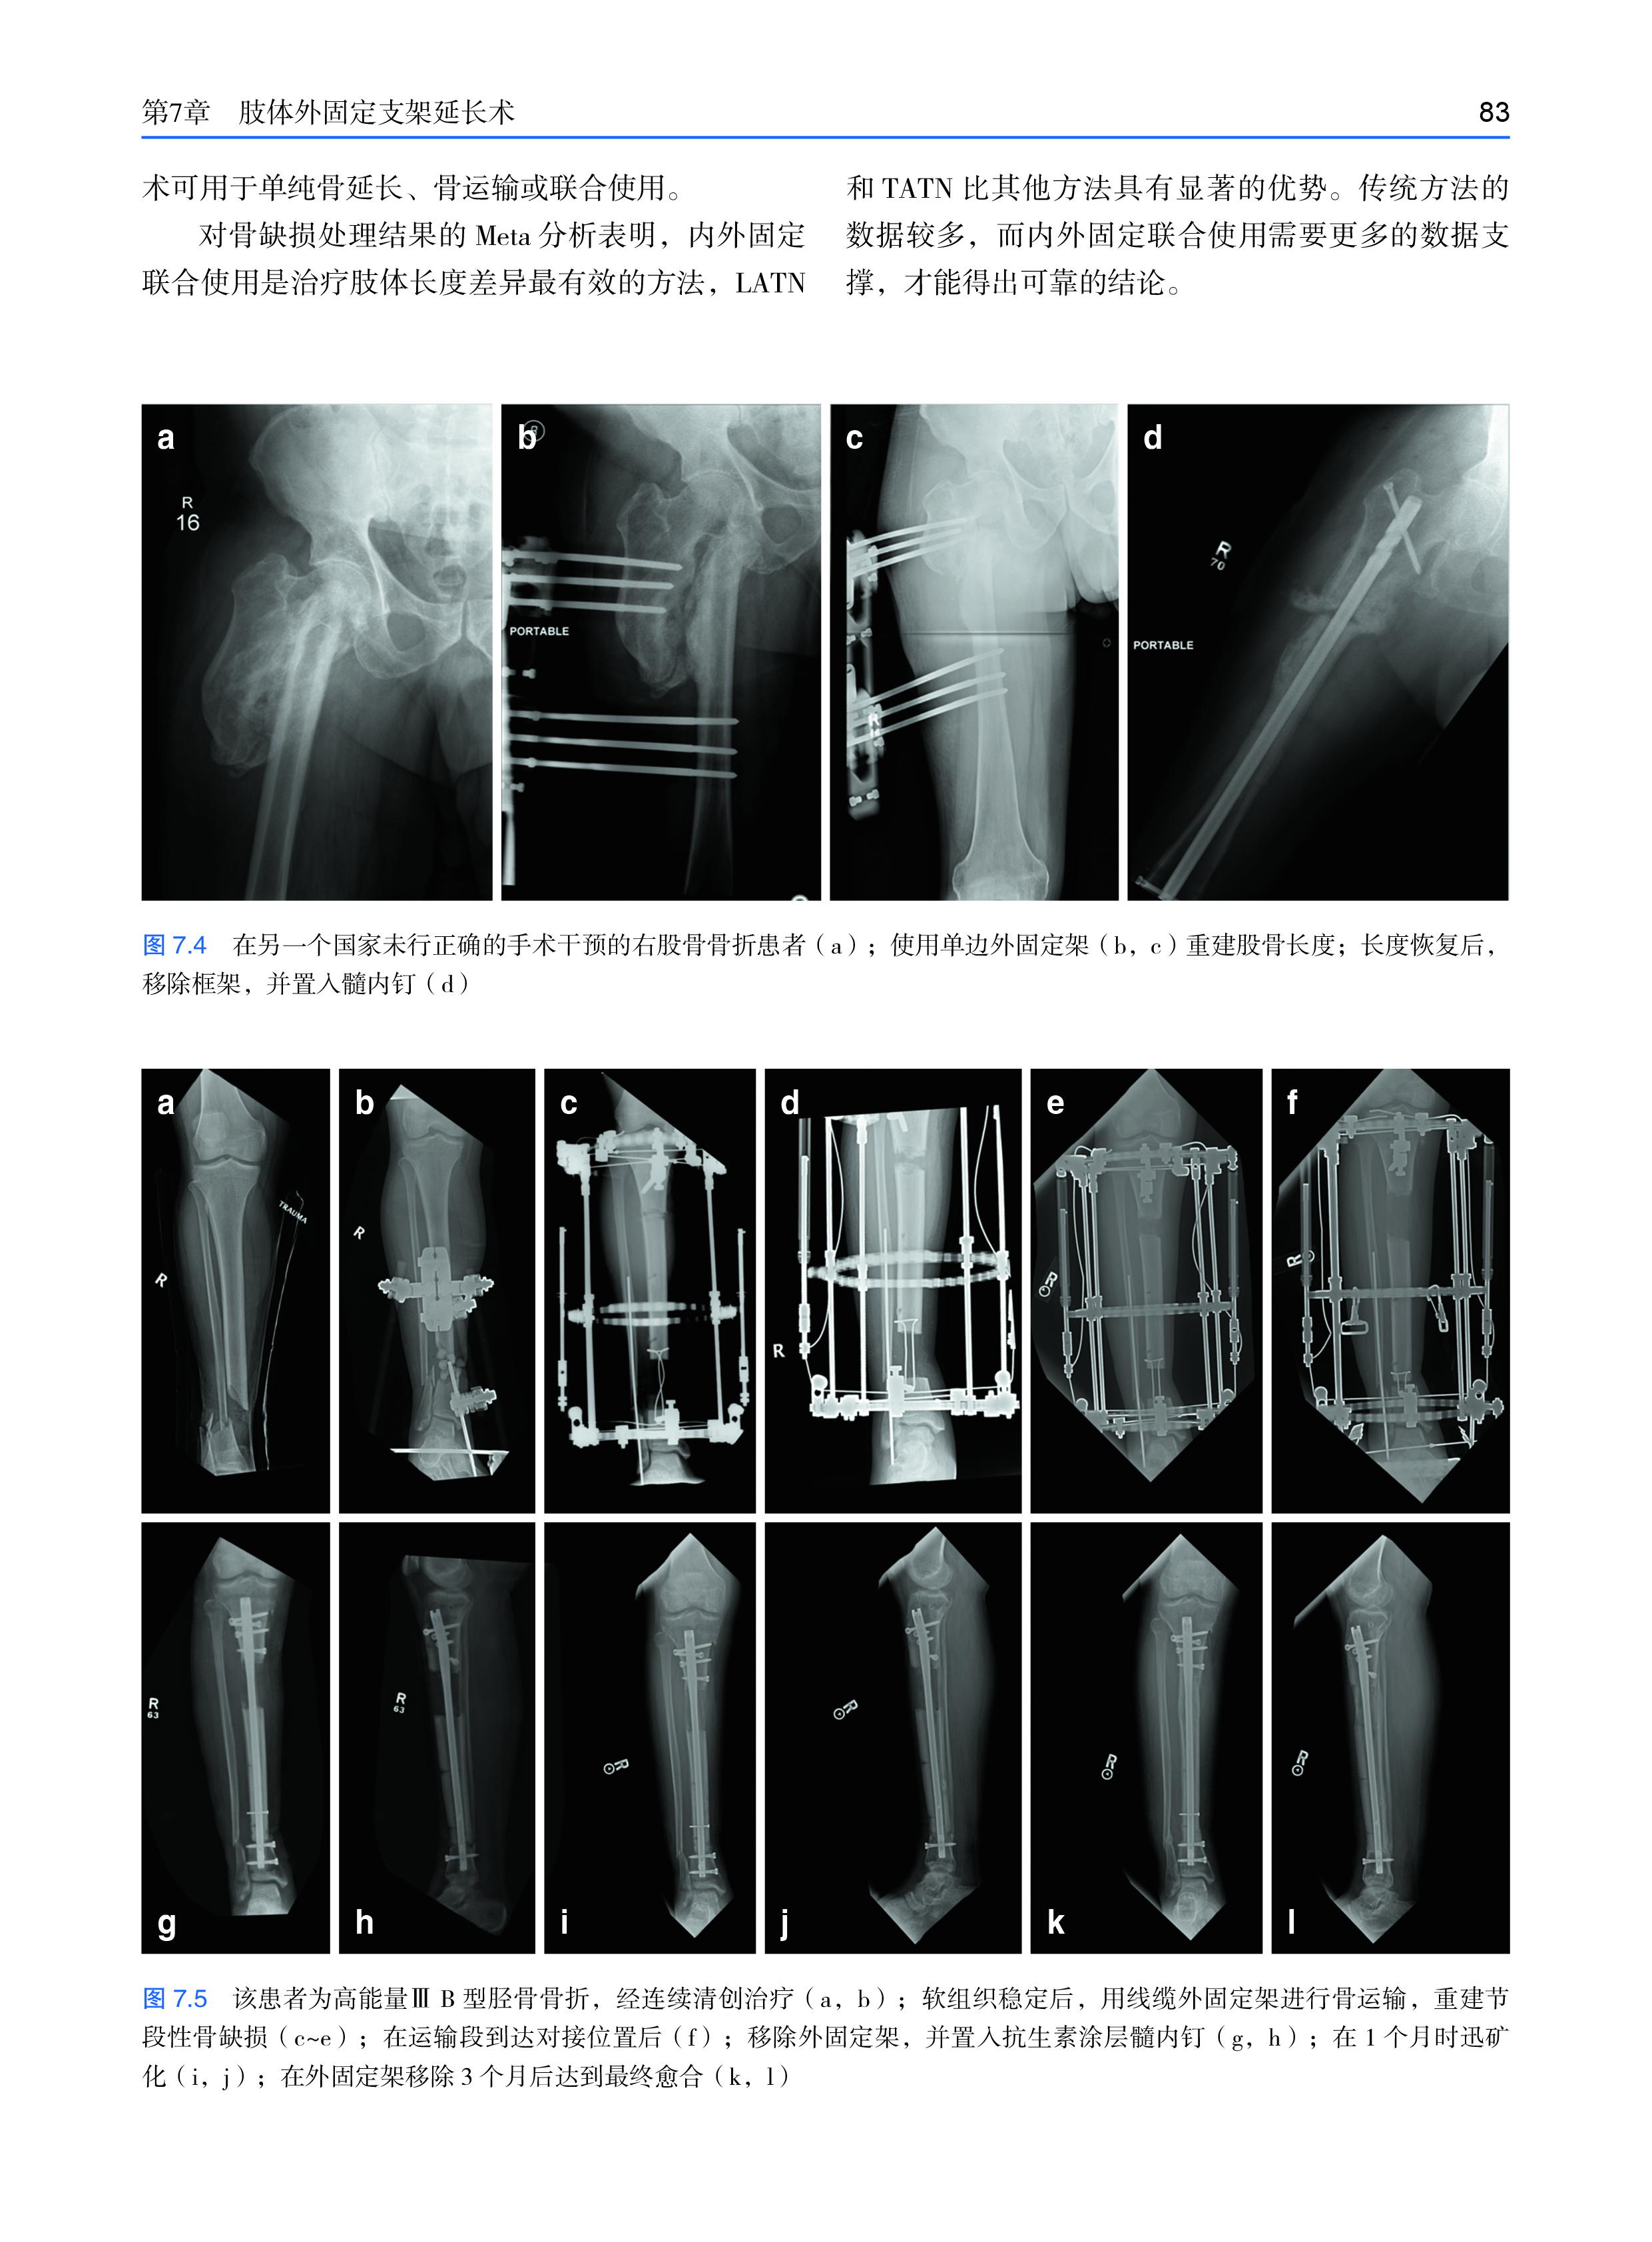

页 数:296

全书共分五章,开篇介绍了与骨骼和关节相关的应力和应变,以及它们与骨折和骨折愈合的关系。第二部分讨论了外固定治疗骨干和关节周围骨折、肢体延长和畸形矫正的生物力学原理。第三部分讨论了尺骨鹰嘴骨折和髌骨骨折的张力带连接,第四部分讨论了锁定钢板和非锁定钢板。最后一章介绍各种骨折和骨不连的髓内钉的生物力学原理,以及关节固定术等。